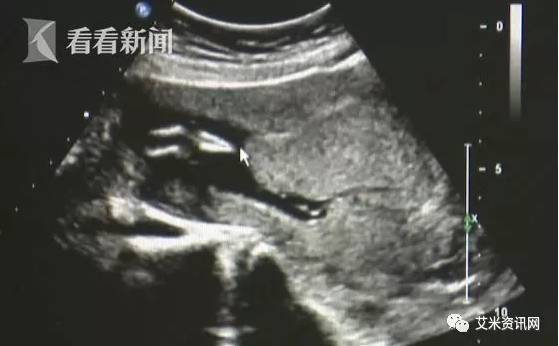

10月上旬,江苏一医院北区的超声科,来了名40岁的二胎妈妈。原本只是常规的复检,但当天的当班医生袁志宏,发现了不对劲。袁志宏发现,胎儿的小腿骨好像有点交叉。 正常的小孩子,下肢应该是不停地在妈妈肚子里动的 ,呈现外八字形。

胎儿已经三个月,袁志宏再三观察,发现胎儿的小腿一直没有活动。尽管有着20多年的超声科经验,这种情况,袁志宏也是第一次见。袁志宏表示,胎儿的小腿基本上是有点融合的,周边软组织好像也是融合的,看这有些像美人鱼的尾巴。

袁志宏怀疑,这是传说中极为罕见的“美人鱼综合症”,立马让孕妇再去产科确认。

经诊断, 胎儿是多发畸形,人鱼综合症并发的,合并其他的畸形。